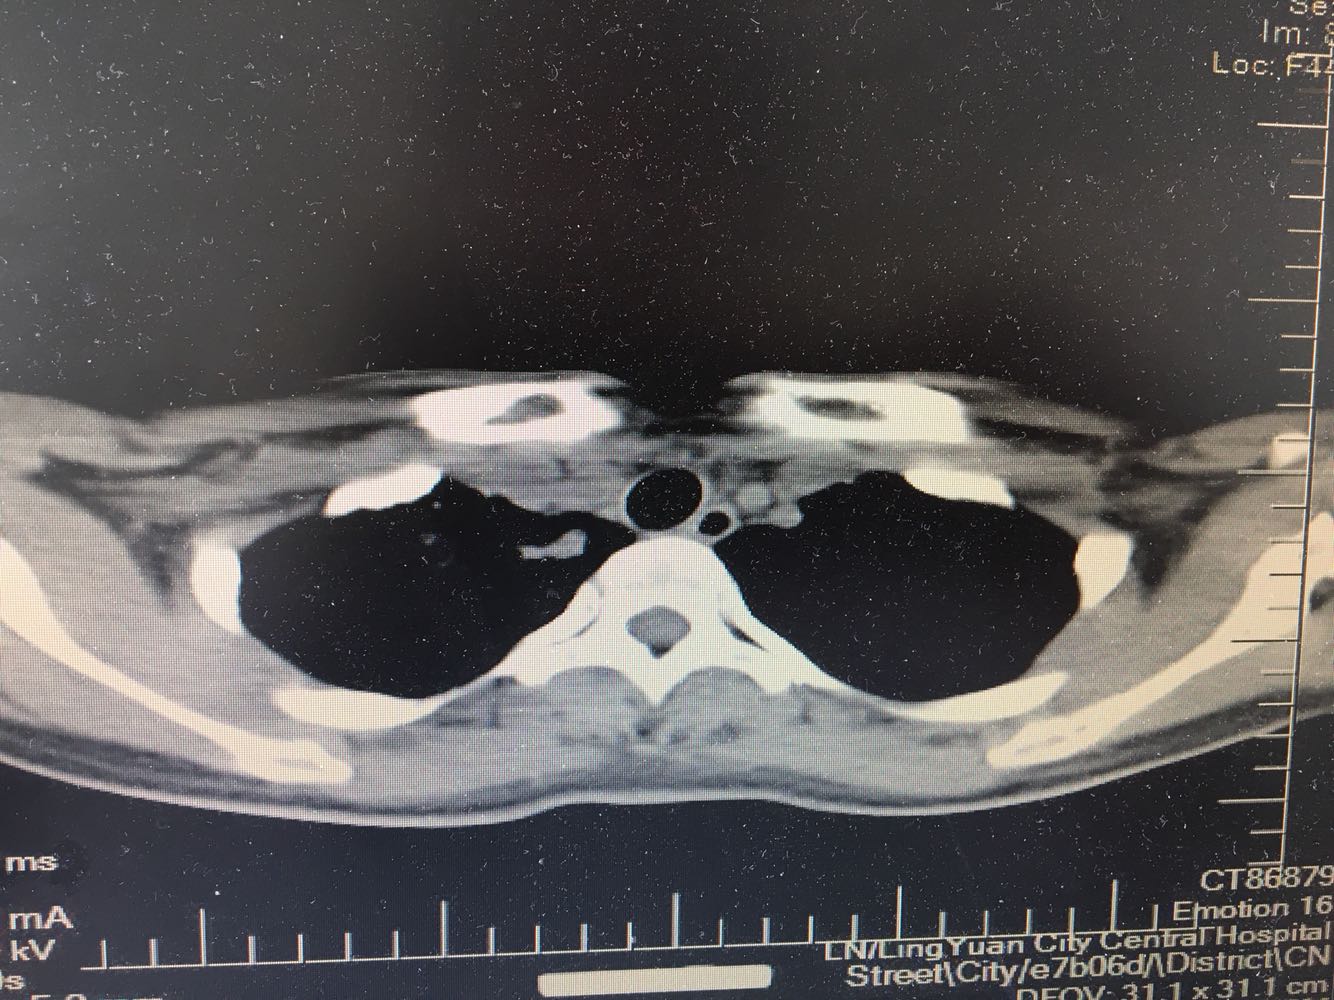

女,26岁,咳嗽1周,咳痰不畅,咽喉痒,口服阿莫西林无好转,昨日发热,体温38.5摄氏度,于门诊查肺CT后以肺炎收入院,病来无盗汗,无咳血,无消瘦及乏力,无头痛,无肢体酸痛,饮食睡眠可,二便正常

支原体肺炎?肺结核?

支原体抗体1:160,结核抗体弱阳性。支原体肺炎个别可见上叶病变,该患无结核中毒症状,考虑支原体肺炎可能性大,但肺尖为结核好发部位,需要抗炎治疗后复查观察疗效。